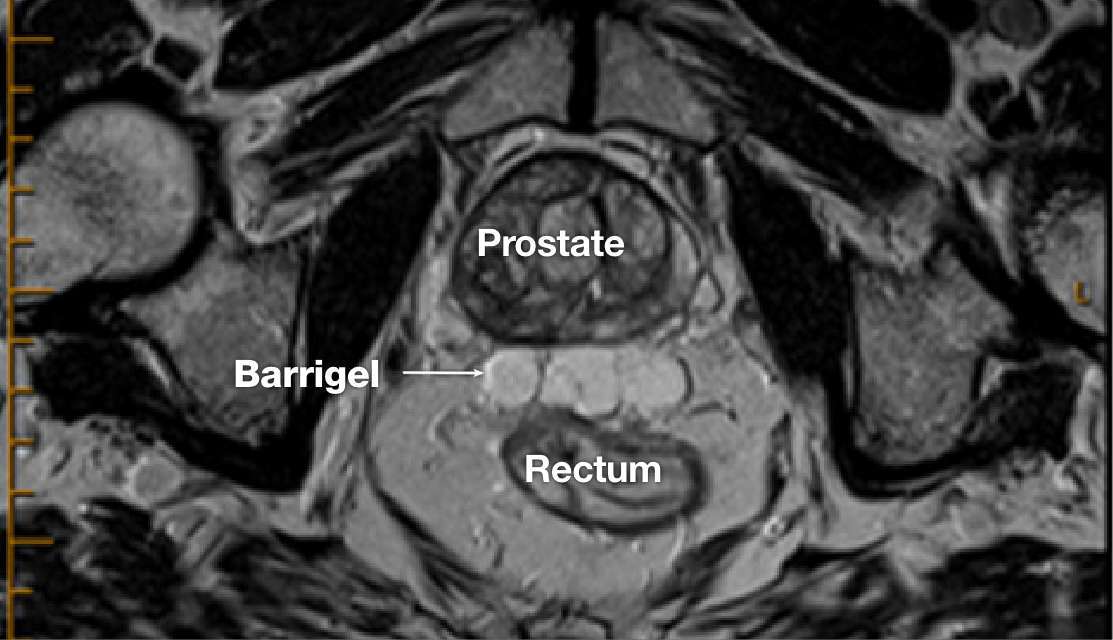

MR image courtesy of Prof Michael Chao, MBBS (Hons), FRANZCR, AFRACMA, DMedSc, Radiation Oncologist; Victoria, Australia